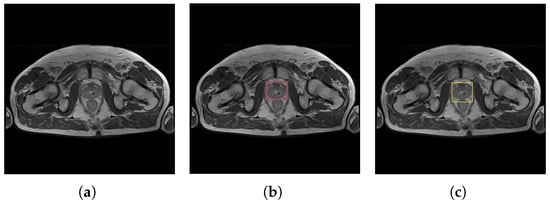

Eight-bit 256 × 256 color images and binary masks were used to train U-Net. During the labeling stage, Dicompyler software added 15 px padding to simulate the output resulting from YOLOv4. An example is presented in Figure 3.

Figure 3.

Example of training data presented to the U-net model: (a) input data with the prostate region, and (b) the corresponding reference ground truth prostate mask.